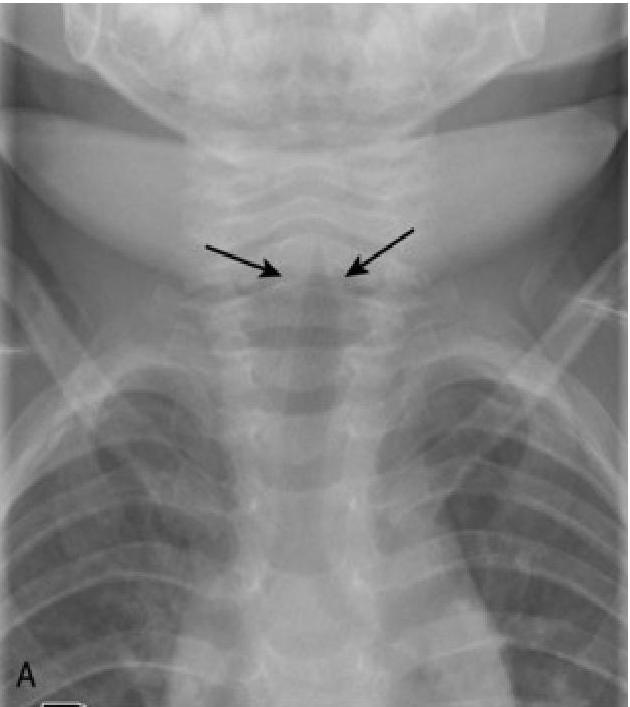

- The “Steeple Sign”: Characteristic subglottic narrowing seen on X-ray.

- X-ray, steeple sign